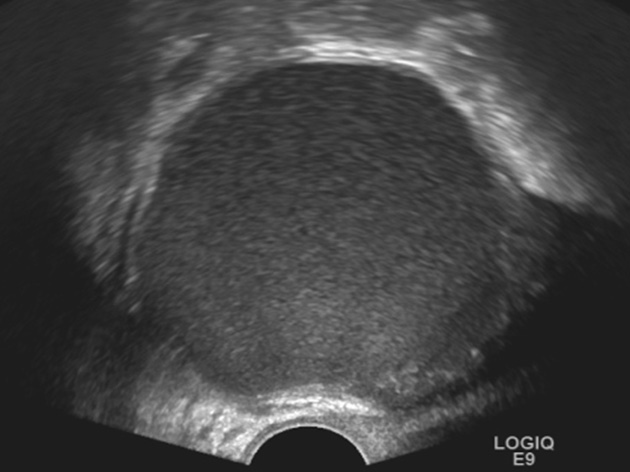

К «практически наверняка доброкачественным» относятся образования, имеющие «классическую» эхографическую картину доброкачественного образования (простая и однокамерная киста, геморрагическая киста, эндометриома, дермоидная киста и фиброма) (рис. 1–6). Понятие однокамерной кисты относительно новое и подразумевает наличие в полости кисты ≥1 неполной перегородки, локальных утолщений на стенке высотой до 3 мм, внутренних эхо в полости (рис. 2). Одиночная тонкая (≤3 мм) перегородка в полости кисты считается доброкачественной находкой [22].

Рис. 1. Простая киста яичника. Анэхогенное аваскулярное образование с ровными тонкими стенками, без солидного компонента и перегородок

Fig. 1. Simple ovarian cyst: an anechoic avascular lesion with smooth thin walls, without a solid component and septations

Рис. 2. Однокамерная киста яичника. Киста с одиночной неполной перегородкой и внутренним эхо

Fig. 2. Uniloculated ovarian cyst: a cyst with one incomplete septum and internal echoes